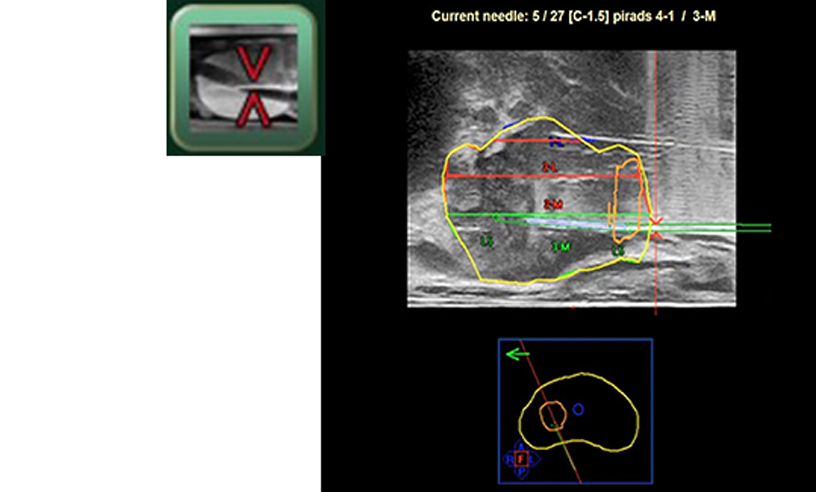

Tedavi ve Takip

ARIETTA 65 IntuitiveFusion, kriyoterapi, yüksek yoğunluklu odaklanmış ultrason (HIFU) ve brakiterapi gibi Odak Terapi planlama yazılımlarına veri kümelerini depolayabilir ve aktarabilir. Kriyoterapi için hedef alanın sıcaklık dağılımının bir simülasyonunu görüntülemek mümkündür *1 . Ayrıca tedavi izleme ve aktif gözetim için de faydalıdır.